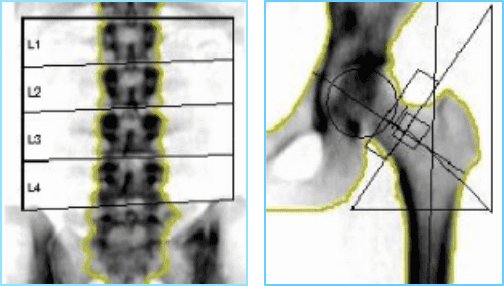

骨塩定量検査

「2種類のエックス線を使用し、骨の強さを測定

2種類の異なるエネルギーのエックス線を使用し、骨と軟部組織のエックス線吸収率の差を利用して骨密度を測定します。腰椎と大腿骨頸部(股関節)の骨密度を測定することで、骨粗しょう症の早期発見や治療効果の判定などに有効です。

この骨塩定量検査は、測定精度が高く検査時間も短いため、骨粗しょう症診断において最も標準的な方法です。

骨密度の計測画像

筋肉量、体脂肪率の計測画像